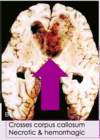

What characteristic of Glioblastomas is seen on MRI?

Ring-enhacing lesions

Which tumor often crosses the corpus callosum and produces a “butterfly” appearance

Glioblastoma

Contrast ring enhancing lesions, with hypodense central necrosis is characteristic of what kind of tumor?

Glioblastoma